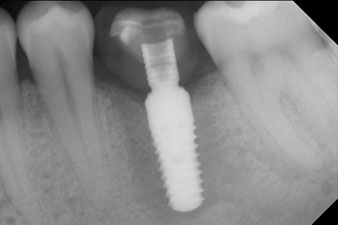

Röntgenkontrolle

Abb. 10: Die Röntgenkontrolle zeigt die erfolgreiche Osseointegration und die spaltfrei verschraubte Krone.